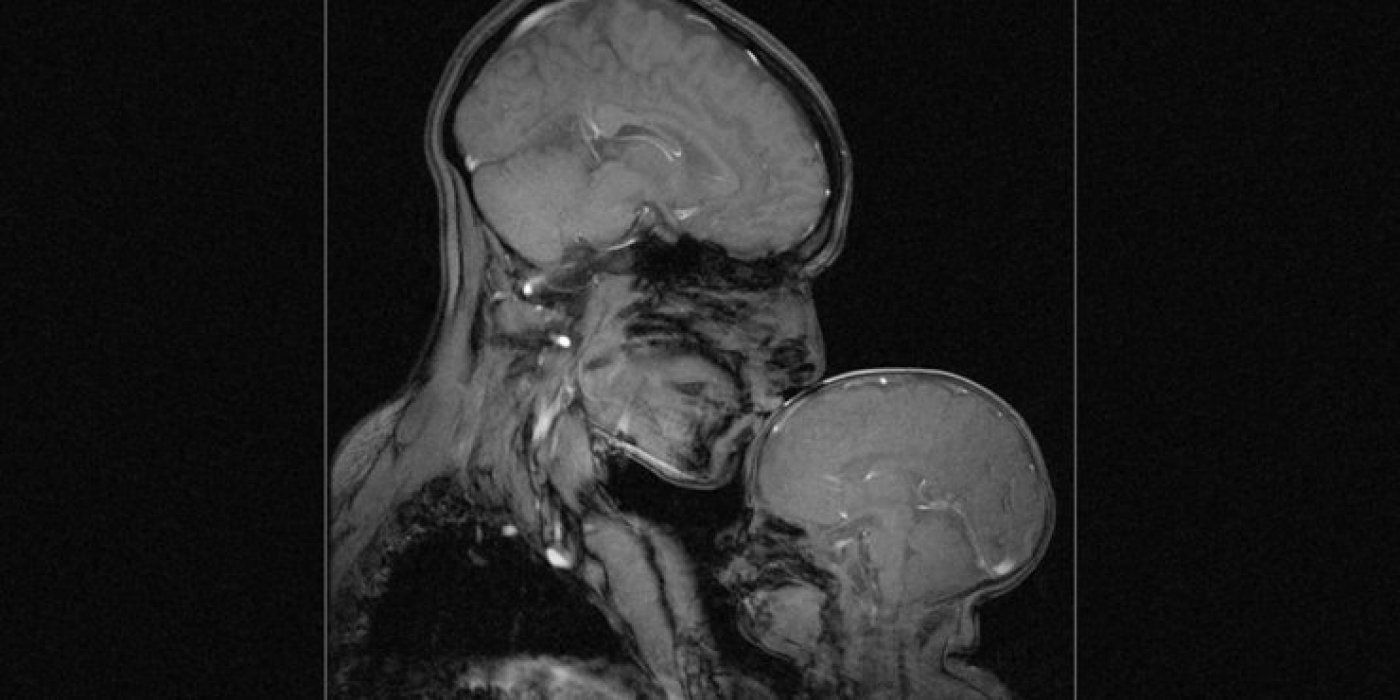

Gledate u prvu sliku magnetske rezonancije (MRI) koja prikazuje vezu majke i djeteta, a koju je snimila neuroznanstvenica Rebecca Saxe. Slika zapravo prikazuje Rebeccu i njezinog dvomjesečnog sina Percyja.

Možda najneočekivaniji dio slike je kako se vide razlike između djetetovog i majčinog mozga. Bebin mozak je glatkiji i tamniji jer ima značajno manje bijele tvari. Bijela tvar ili bijela masa sastoji se od glijinih ćelija i mijelina koji prenose signale iz jedne regije u mozgu u drugu i između mozga i nižih moždanih centara, odnosno 'komuniciraju' poruke unutar mozga. Taj nedostatak mijelina gotovo kao da se čini kao stvaran vizualni primjer toga kako majke doslovno oblikuju i formiraju svoju djecu od rođenja. Način na koji govorimo, pjevamo, držimo i igramo se s bebama oblikuje temelje mozga kako dijete raste.

Kao mnoge majke, Rebecca je provela nesrazmjernu količinu vremena gledajući svoju bebu. No, zbog toga jer je kognitivna neuroznanstvenica, za nju je gledanje bebe bilo malo drugačije. Konkretno, provela je mnogo vremena gledajući kako se mozak njezine bebe razvija kroz uređaj za magnetsku rezonanciju. Proučavala je kako je očaravajuće gledati kako dječji mozak odgovara na interakciju s odraslima, kako se krvne žile proširuju u mozgu i kako protječu u odgovoru na pjesme i priče u majčinom glasu.

"Majka i dijete predstavljaju snažan simbol ljubavi i nevinosti, ljepote i plodnosti. No, ja sam neuroznanstvenica i radila sam kako bih snimila ovu sliku, ali također sam i majka u njoj, sklupčana unutar nje, zajedno sa svojim sinom", rekla je Rebecca. Uostalom, slika je fascinantna i prekrasna vizualizacija onoga što ostaje nevidljivo u našem životu, a što je ponekad - najsnažnije od svega!